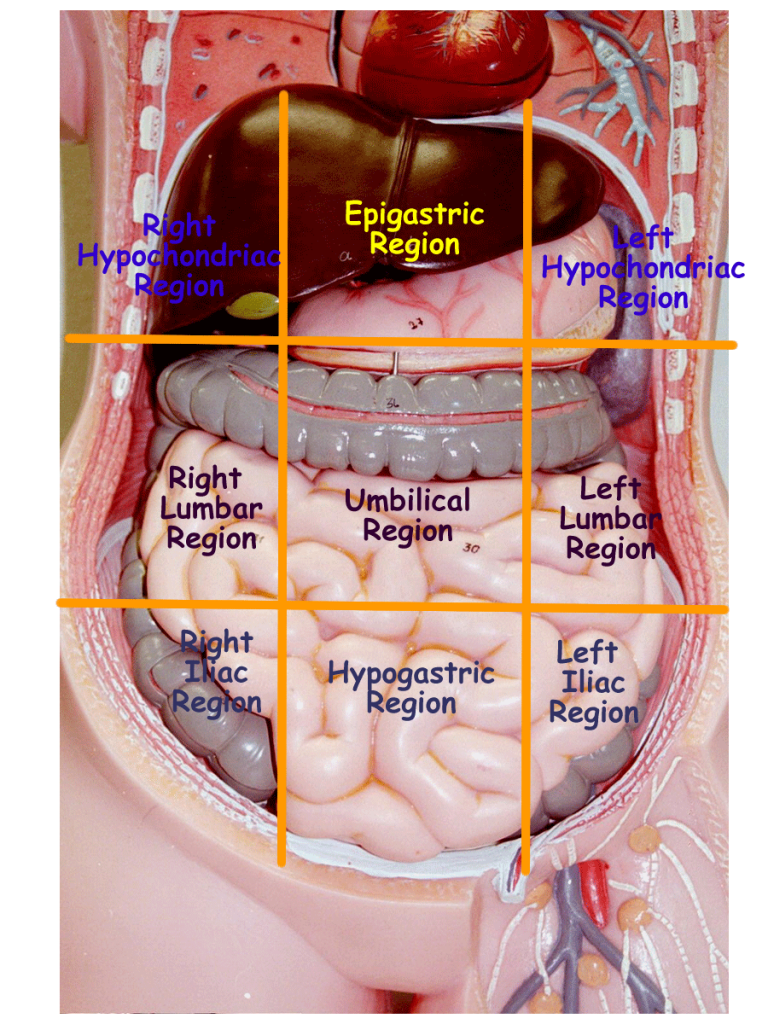

www.alamy.comAbdomen - Wikipedia, La Enciclopedia Libre

www.alamy.comAbdomen - Wikipedia, La Enciclopedia Libre

es.wikipedia.orgabdomen organs stomach abdominal internal organ rib locations ribs cage spinal projections labeled spine navel anatomical lumbar

es.wikipedia.orgabdomen organs stomach abdominal internal organ rib locations ribs cage spinal projections labeled spine navel anatomical lumbar

Diagram Of The Abdominal Organs

guidelibmisjoinder.z22.web.core.windows.netUnderstanding Abdominal Divisions | Anatomy Snippets | Complete Anatomy

guidelibmisjoinder.z22.web.core.windows.netUnderstanding Abdominal Divisions | Anatomy Snippets | Complete Anatomy

completeanatomy.cnAbdomen (Human Anatomy) - Image, Definition, Function, Diseases And More

completeanatomy.cnAbdomen (Human Anatomy) - Image, Definition, Function, Diseases And More